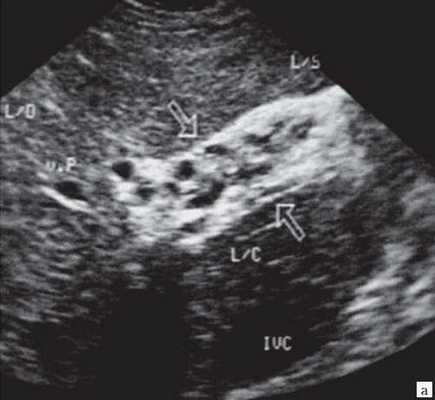

- Ультразвуковое исследование (УЗИ). Основным признаком МЖ при УЗИ является расширение внутрипеченочных желчных протоков (рис. 1). УЗИ позволяет не только выявить билиарную гипертензию, но и установить уровень блока.

При высоком билиарном блоке (обтурация на уровне ворот печени) при УЗИ визуализируются расширенные внутрипеченочные протоки при нормальном диаметре ОЖП (до 6 мм), желчный пузырь чаще нормальных размеров или уменьшен, возможно выявление в воротах печени объемного образования.

При низком билиарном блоке (обтурация на уровне холедоха, головки ПЖ, БДС) кроме расширенных внутрипеченочных протоков визуализируются расширенные внепеченочные протоки, желчный пузырь увеличен (рис. 2).

Рис. 1. Ультразвуковая картина билиарной гипертензии при механической желтухе.

а) Расширенные внутрипеченочные протоки.

б) Увеличенный желчный пузырь с густой взвесью (красная стрелка) и расширенный ОЖП (синяя стрелка).